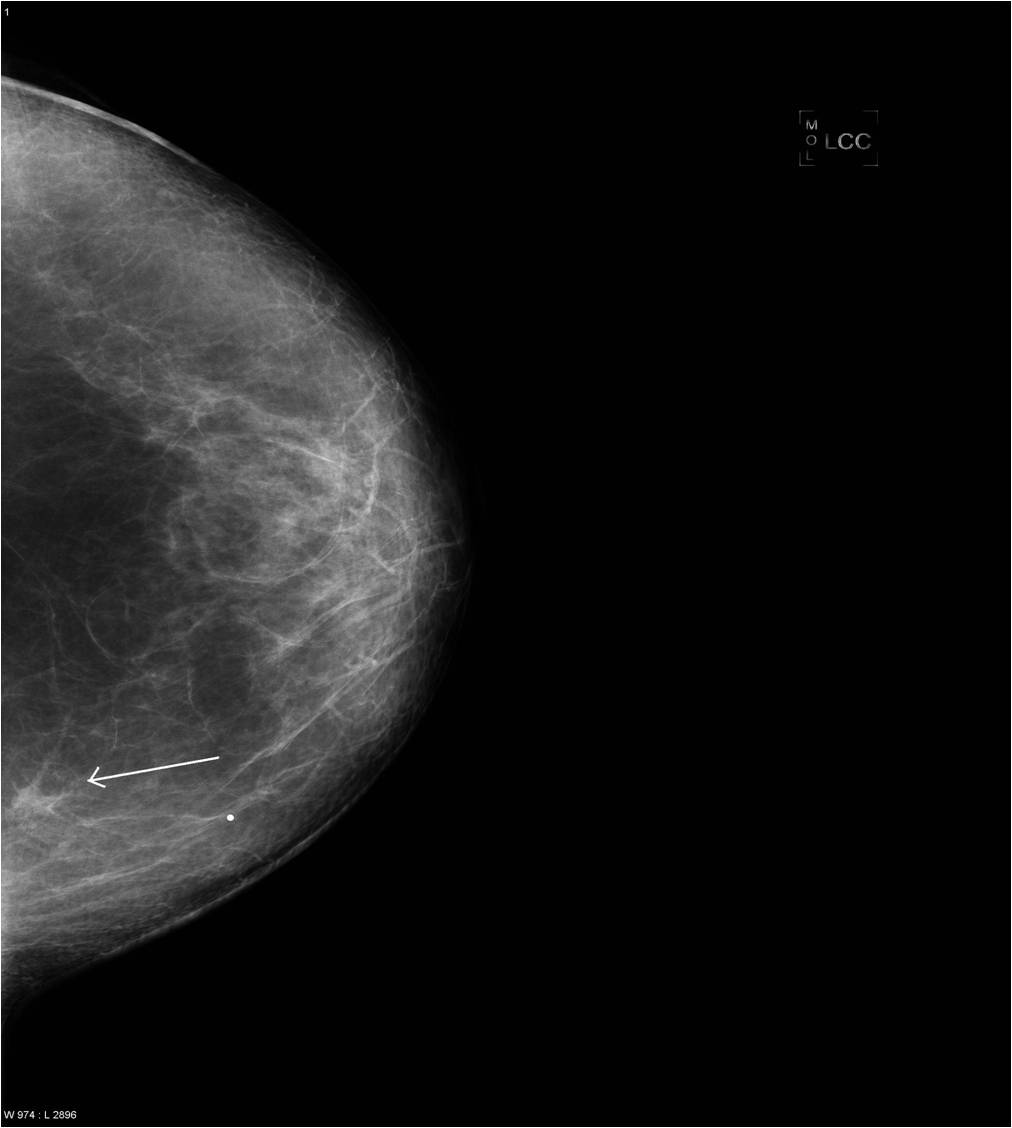

Pathologic lesions in the breast appear as various shapes and densities of soft tissues or calcificications or as the combinations of these two on mammography (Picture 16.). At many times only a few scattered, ill-defined, pleiomorphic microcalcifications indicate the presence of a pathologic lesion.

The soft-tissue lesions can appear as well-defined, rounded or oval shaped (Pictures 13.,14.) or as ill-defined, star-shaped masses (Picture 15.). Rounded or oval lesions are in most cases benign and their malignant proliferation is rare, they do not require surgical removal. These lesions are usually cysts and fibroadenomas, at other times hamartomas, lipomas and at very few times malignant tumors.

Star-shaped lesions are very typical of malignant tumors.

o “White star”: describes the tumor body with dense spiculations of various lengths appearing around the core = carcinoma

o “Black star”: there is no tumor body, the central part is transparent. The spiculations are arched, long and thin. These usually do not indicate the entity of the lesion; they can either be benign or malignant. Examples are lobular carcinoma, post-radiation scar tissue, fatty necrosis or postoperative scar tissue (patient history is indicative!).